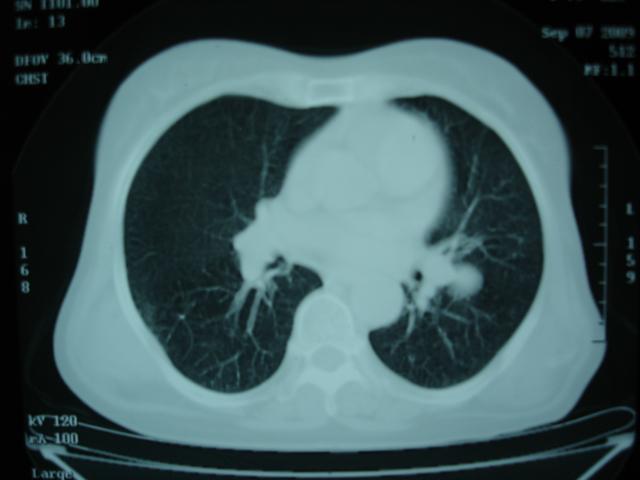

以下是引用卜一在2009-9-7 19:51:00的发言:[br][br] 1 左侧胸内甲状腺占位-多考虑甲状腺腺瘤! 2、左肺门占位-建议增强扫描以便明确性质。 3 慢支并感染! [br]

以下是引用shibing在2009-9-7 20:40:00的发言:[br]左侧胸内甲状腺占位-多考虑甲状腺腺瘤! 2、左肺门占位-建议增强扫描以便明确性质。 3 慢支并感染! [br]